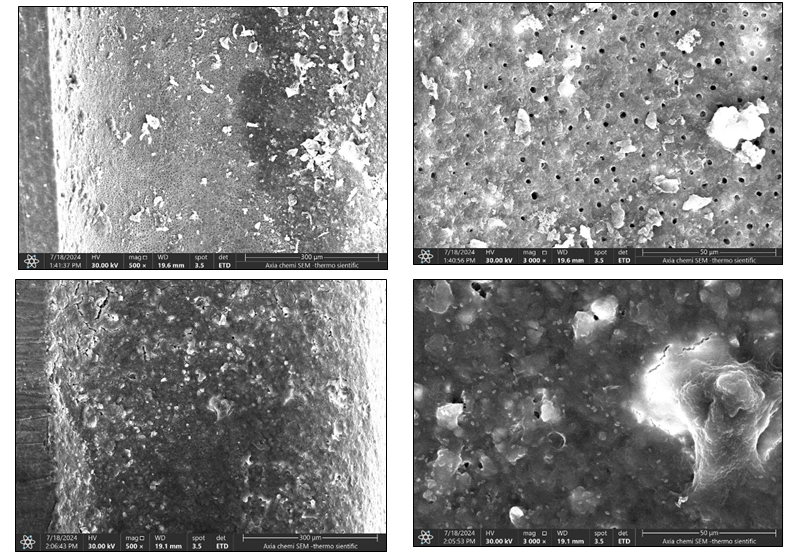

Background: This vitro study investigated the effectiveness of Er,Cr:YSGG laser-activated irrigation in removing root canal filling remnants during endodontic retreatment. The technique used photon-induced photoacoustic streaming (PIPS) at 700 μs pulse duration to activate 2.5% sodium hypochlorite (NaOCl) and 17% EDTA. Materials and methods: Twenty-one extracted human maxillary and mandibular premolars with single roots were instrumented and obturated using gutta-percha and a bioceramic root canal sealer. After retreatment using nickel-titanium rotary files (XP-endo Retreatment), the specimens were randomly assigned into three groups (n=7 per group) according to the irrigation technique: Group 1: conventional syringe irrigation (control), Group 2: passive ultrasonic irrigation, Group 3: laser-activated irrigation using Er, Cr:YSGG laser (2780 nm, 700 μs pulse duration, 5 Hz, 1 W, RFT2 tip, with no air or water spray). All samples were sectioned longitudinally and examined under a scanning electron microscope (SEM) to assess the presence of residual filling materials in the coronal, middle, and apical thirds. Cleanliness scores were assigned by two calibrated endodontists based on a 4-grade scoring system and were statistically analyzed using one-way ANOVA followed by Tukey’s post hoc test. The significance level was set at α = 0.05. Statistical analysis revealed a significant difference among the groups (P < 0.05). Group 3 showed significantly lower residual debris compared to Groups 1 and 2 across all root thirds, while the difference between Groups 1 and 2 was not statistically significant (P > 0.05).

Results: Group 3 (n = 7) exhibited significantly lower residual debris compared to Groups 1 and 2 across all canal thirds (P < 0.05). The mean cleanliness scores were highest in the coronal third, followed by the middle and apical thirds. No statistically significant differences were observed between Group 1 and Group 2 (P > 0.05), suggesting limited effectiveness of ultrasonic irrigation compared to laser activation.